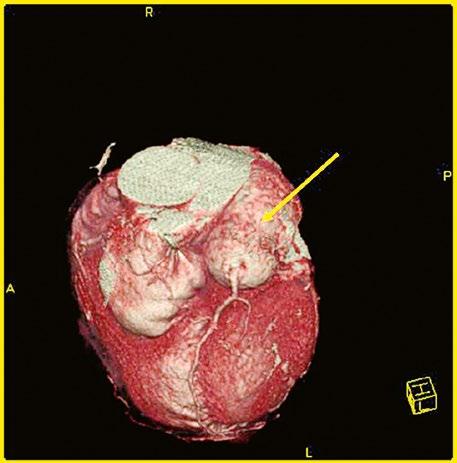

Obr. 45.11 CT angiografie, defekt typu sinus venosus superior je označen hvězdičkou, anomální pravá horní plicní žíla ústící do horní duté žíly je označena šipkou

PS – pravá síň, LS – levá síň

Obr. 45.12 CT angiografie s 3D rekonstrukcí u pacientky s defektem typu sinus venosus superior a s parciálním anomálním návratem dvou pravostranných plicních žil z horního a středního laloku do horní duté žíly, pravá dolní plicní žíla ústí normálně do levé síně